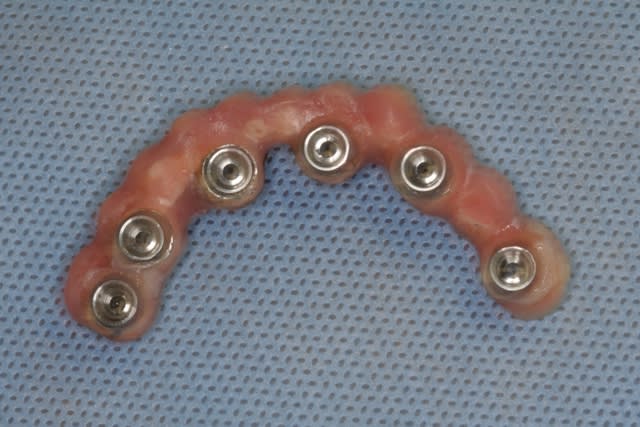

bon, et bien c'est fait!

comme promis, et avec la bénédiction de posit, voici quelques morceaux choisis de cette journée...

ah, oui, j'allais oublier au maxillaire 8 legacy3 diamètre 3.7mm et en 13 de long (sauf 22 en 11.5mm)

mandibule 6 implants de 13mm et 3.7mm de diamètres (sauf 36 et 45 en 4.2mm/13)